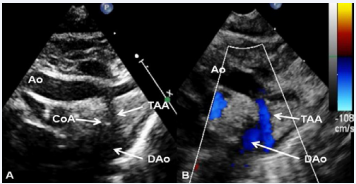

Imaging and Doppler interrogation from a suprasternal notch view may show aortic coarctation (Figure 11), which is common in patients with associated transposition of the great arteries (Type II).

Figure 11 Selected video frames from suprasternal notch views of the aortic (Ao) arch in 2D (A) and color flow (B) images of a neonate with tricuspid atresia and transposition of the great arteries demonstrating coarctation of the aorta (CoA) and hypoplastic transverse aortic arch (TAA). The association of CoA with tricuspid atresia plus transposition of the great arteries is well known [36].

Figure 11: Selected video frames from suprasternal notch views of the aortic (Ao) arch in 2D (A) and color flow (B) images of a neonate with tricuspid atresia and transposition of the great arteries demonstrating coarctation of the aorta (CoA) and hypoplastic transverse aortic arch (TAA). The association of CoA with tricuspid atresia plus transposition of the great arteries is well known [36].